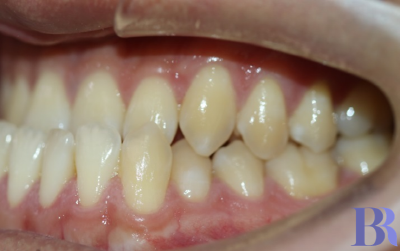

초진 입안사진입니다

치아가 거꾸로 물리고 있으나

실제 골격이 나온것에 비해서는

덜 나와 보이네요.

양악수술 대상자의 전형적인

치아 상태를 볼수 있습니다.

치성보상작용으로 인해

실제 골격에 비해 치아 간격이

좁아 보입니다

아랫니와 윗니 앞뒤 차이가

외모에 비해 심하지는 않습니다